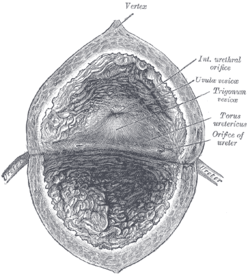

Anatomy of the bladder and outlet

The main organs involved in urination are the urinary bladder and the urethra. The smooth muscle of the bladder, known as the detrusor, is innervated by sympathetic nervous system fibers from the lumbar spinal cord and parasympathetic fibers from the sacral spinal cord.[4] Fibers in the pelvic nerves constitute the main afferent limb of the voiding reflex; the parasympathetic fibers to the bladder that constitute the excitatory efferent limb also travel in these nerves. Part of the urethra is surrounded by the male or female external urethral sphincter, which is innervated by the somatic pudendal nerve originating in the cord, in an area termed Onuf's nucleus.[5]

Smooth muscle bundles pass on either side of the urethra, and these fibers are sometimes called the internal urethral sphincter, although they do not encircle the urethra. Further along the urethra is a sphincter of skeletal muscle, the sphincter of the membranous urethra (external urethral sphincter). The bladder's epithelium is termed transitional epithelium which contains a superficial layer of dome-like cells and multiple layers of stratified cuboidal cells underneath when evacuated. When the bladder is fully distended the superficial cells become squamous (flat) and the stratification of the cuboidal cells is reduced in order to provide lateral stretching.